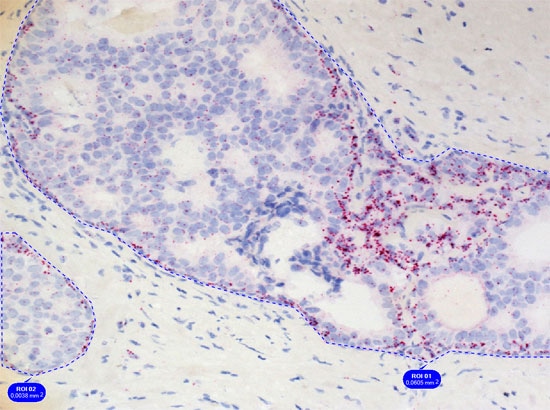

Simple context based analysis can easily be done in HistoQuest by using manual region tools. Drawing the regions takes a negligible amount of time and provides data for epithelial areas and stroma separatelyin this example.